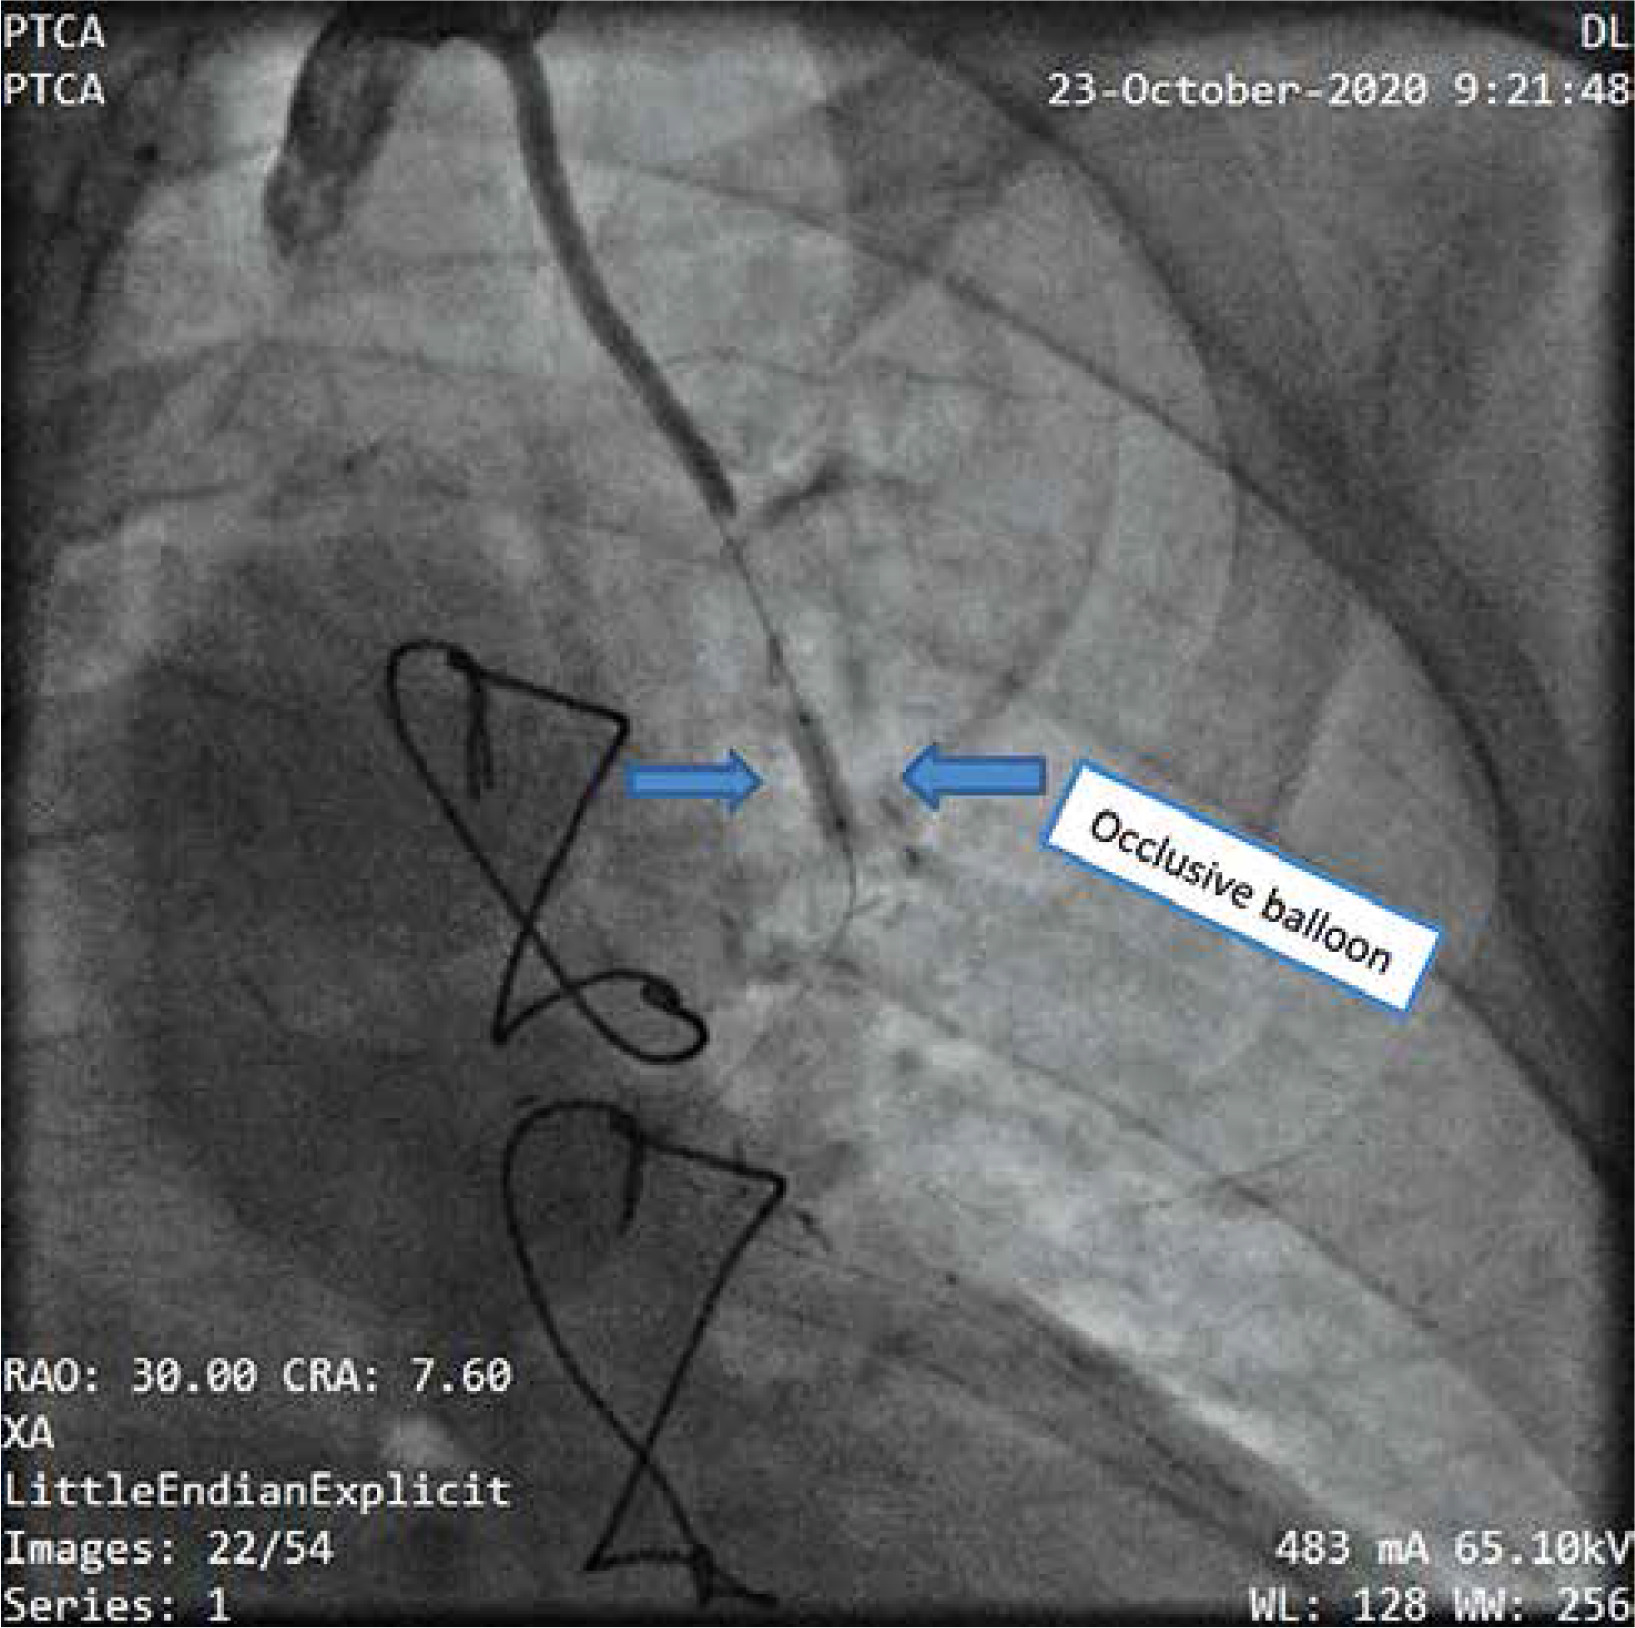

In such cases, for the last 6 years, a method with angiographic balloon occlusion of the LIMA has been used. All patients had previously undergone LIMA grafting of the left anterior descending coronary artery, and, in all cases, preoperative angiography had confirmed the patency of the graft. After signing informed consent forms, the patients were taken to the cardiac catheterization laboratory immediately before reoperation. A common left-femoral approach was used, and systemic heparin (70 IU/kg) was administered. A 6F sheath was placed and an IMA guide catheter was inserted to cannulate the IMA and to obtain posteroanterior and left anterior oblique angiographic views of the IMA graft. The IMA size, estimated visually, varied from 2.0 to 3.5 mm in our patients (Figure 1). A Hi-Torque Balance 0.014-inch coronary guidewire was then positioned into the IMA, followed by an over-the-wire balloon that was 15 mm long with a nominal diameter of 2.0 to 3.5 mm. The balloon was briefly inflated at the nominal pressure (6 atm), and angiography was performed to ensure occlusion of the LIMA graft (Figure 2). The balloon was then left, deflated, in a relatively straight segment of the proximal IMA.

The patients were then transferred to the operation room for routine placement of monitoring lines and anesthetic induction. Re-sternotomy was begun, and the patients were placed on total cardiopulmonary bypass. Aortic cross-clamping and intermittent ante- and retrograde cold-blood cardioplegic arrest were used in all patients for myocardial protection. Deep hypothermic circulatory arrest was not required in any patient. At the time of aortic cross-clamping, the LIMA balloon was inflated at nominal pressure (6 atm) to occlude the IMA. The balloon was deflated at the time of aortic cross-clamp release and before the appointment of protamine, the balloon and the guide are removed. Only the arterial port is left, which is explanted postoperatively. All IMA grafts were found to be patent, with no significant narrowing. The IMA balloon was inserted successfully in all cases, and no complications were encountered during preoperative catheterization. Satisfactory occlusion of LIMA flow with inflation of the endoluminal balloon was seen on preoperative angiography in all patients. Endoluminal occlusion of the LIMA graft was performed intraoperatively in all cases, and no patient required external occlusion of the graft.